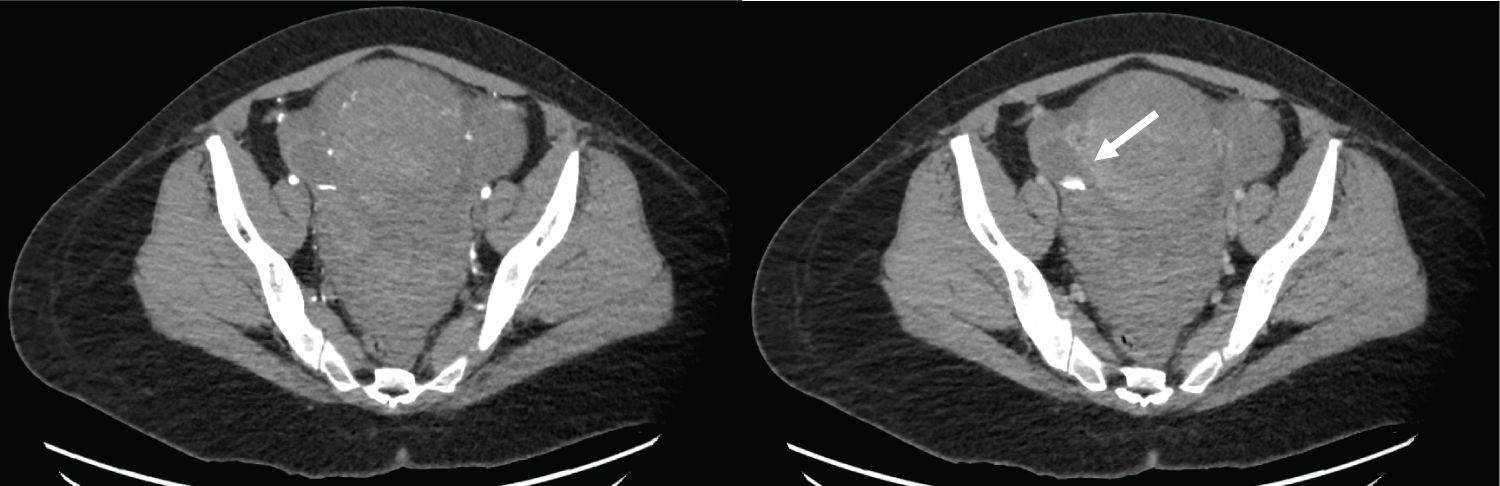

Gestational age at time of induction was 40 weeks 3 days. Prostaglandins were used for priming of the cervix, followed by an artificial rupture of the membranes, and starting an intravenous drip of oxytocin. Epidural analgesia was used for pain relief in labor. Cervix reached full dilation after approximately 10 hours. She had an uneventful vaginal delivery after a short second stage of labor. A female neonate was born with a birth weight of 4060 g. Third stage of labor was uncomplicated. Estimated vaginal blood loss was 150 cc. Two hours after delivery, she suddenly became hypotensive and tachycardic, with diagnosis of a hypovolemic shock. Clinical examination showed an abdominal tenderness and bedside-ultrasound showed a large amount of free fluid intra-abdominally. There was no abnormal vaginal bleeding. An urgent CT abdomen was performed, showing a large amount of free fluid, reaching from the pelvic cavity up to the peri-splenic and peri-hepatic areas. Absence of contrast enhancement in the anterior uterine wall was compatible with possible uterine rupture. Furthermore, a contrast-extravasation on arterial phase was described on the posterolateral right side of the uterus, indicative for an arterial hemorrhage. There was no indication for embolization. An urgent laparotomy, using midline incision, was performed. Two grams of cefazoline, two units of packed cells and carboprost were given pre-operatively. A hemoperitoneum was diagnose perioperatively with 3000 cc of blood intra-abdominally. Primary focus of the bleeding was located on the posterior right side of the uterus, as a lateral branch of the uterine artery in the parametrium. Bleeding stopped after hemostatic sutures and clipping of the vessel. Uterus was intact with no signs of uterine rupture, in contrast to what was suggested on imaging. There was no visible abnormal anatomy of uterine vessels suggesting possible aneurysm. Since the sutures were placed in the anatomical proximity of the ureter, its course was thoroughly explored with no signs of ureteral injuries. A methylene blue test at cystoscopy was also performed, with normal results. At the end of the surgery, a surgical drain was inserted in the pelvic cavity that could be removed on day 4. Postoperative follow-up was without events. 1 unit of packed cells was administered, given the postoperative hemoglobin level of 7.2 g/dL. She was discharged ten days postpartum. A neurological examination one month postpartum showed a hypoesthesia of the right nervus cutaneus femoralis lateralis with preserved sensibility. Spontaneous recuperation is to be expected (Figure 1, Figure 2 and Figure 3).

Figure 1: a) Axial early arterial phase; b) Portal venous phase images show contrast extravasation related to active bleeding in the right periuterine region (arrow). View Figure 1